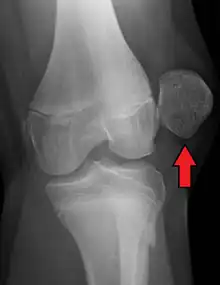

| X-ray showing a patellar dislocation, with the patella out to the side. | |

A patellar dislocation typically occurs when the knee is straight and the lower leg is bent outwards when twisting.[1][2] Occasionally, it occurs when the knee is bent and the patella is struck directly.[1] Commonly associated sports include soccer, gymnastics, and ice hockey.[2] Dislocations nearly always occur away from the midline.[2] Diagnosis is typically based on symptoms and supported by X-rays.[2]